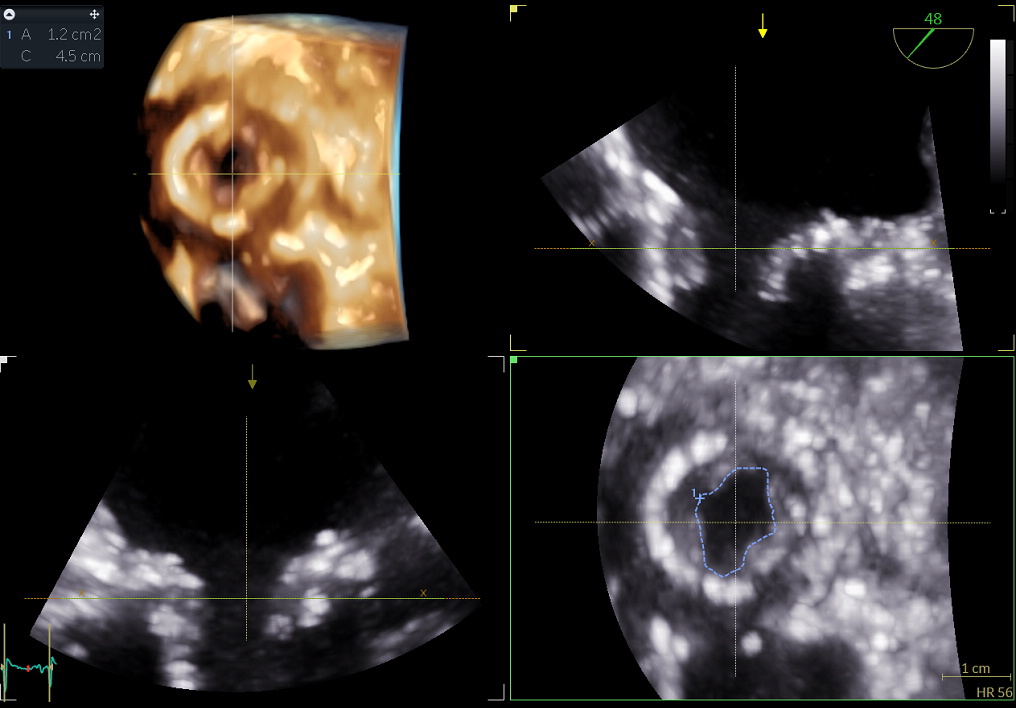

Im Juni 2024 kam es zu einer kardialen Dekompensation mit Zunahme des mittleren Gradienten auf 27mmHG (Abbildung 1) und einem NTproBNP von 21,487ng/l. Die Echokardiografie ergab ein zunehmendes Rechtsherzversagen mit konsekutiv fehlender Füllung des linken Ventrikels und weiterer Verengung des LVOTs. Am zweiten stationären Tag kam es zu Kammerflimmern mit Reanimation. Bei fehlenden Therapiealternativen wurde als Bail Out Strategie mit Hilfe eines Inari FlowTriever® Systems nach transseptaler Punktion das weiche aufgelagerte Gewebe im Bereich des biologischen Mitralklappenersatzes unter transösophagealer echokardiografischer Steuerung aspiriert. Periinterventionell konnte eine Reduktion des Druckgradienten von zuletzt 27mmHg auf 6mmHg (Abbildung 2) dokumentiert werden ohne neue Insuffizienzkomponente der Prothese. Die initiale Öffnungsfläche betrug nur 0,3cm². Nach Aspiration und Debridement betrug die Klappenöffnungsfläche 1,2cm² (Abbildung 3 und 4). Das Aspirat zeigte histologisch ein amorphes eosinophiles Substrat mit Fibrin und Blutbestandteilen. Die echokardiografische Verlaufskontrolle postinterventionell bestätigte einen stabilen Druckgradienten von 6mmHg. Im 3-Monats Follow-Up war die Patientin gut belastbar (NTproBNP von 288ng/l). Eine transösophageale Echokardiografie bestätigt auch nach 3 Monaten eine intakte Prothese.